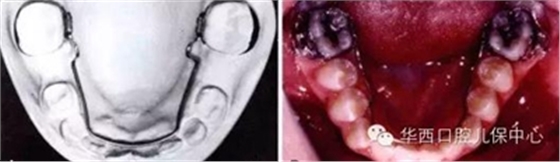

如使用活動(dòng)矯治器拓展間隙: